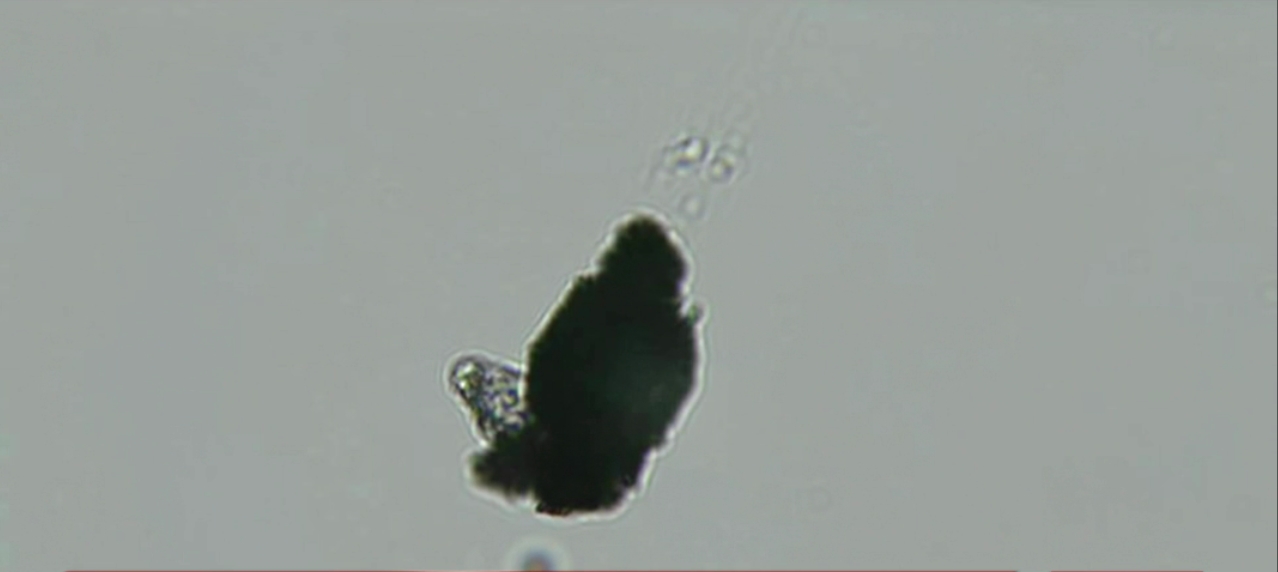

Dr Zandré Botha – Vaccin – 23